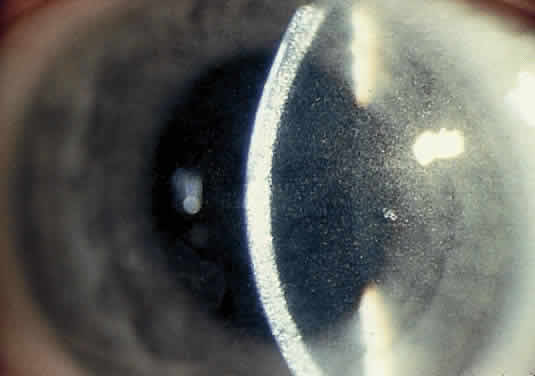

OCULAR FINDINGS. One of the few truly diagnostic and pathognomonic physical signs in clinical medicine is a Kayser-Fleischer corneal pigment ring found in patients with Wilson's disease (Fig. 5).This ring is recognized as a golden-brown, ruby-red, or green band of 1.0 to 3.0 mm, starting at the limbus but at the level of Descemet's membrane.53 The color of the ring is presumably caused by scattering and reflection of incident light and by photointerference effects created by the layers of copper granules. Such variables as size, shape, and unit density of the granules may account for the different appearances of the Kayser-Fleischer ring. The course of the Kayser-Fleischer ring has been well documented.54,55 The site of earliest pigment deposition is an arc in the superior periphery of the cornea from the 10- to 2-o'clock meridian. The arc spreads slowly toward the horizontal plane and gradually broadens. Later in the progression of the ring formation, a band appears inferiorly as a crescent stretching from the 5- to 7-o'clock positions. In time, the two arcs meet. With treatment, the sequence of events is reversed, and after the copper has reabsorbed, a pitted or beaten silver pattern may become apparent at the previous site of the ring. This is an indication that treatment has produced a negative copper balance.49 Decreased visual acuity is not a problem. Rarely, copper is deposited in the crystalline lens, giving an anterior subcapsular “sunflower” cataract.

Fig. 5. Wilson's disease. Kayser-Fleischer peripheral corneal ring. Copper pigment at level of Descemet's membrane.